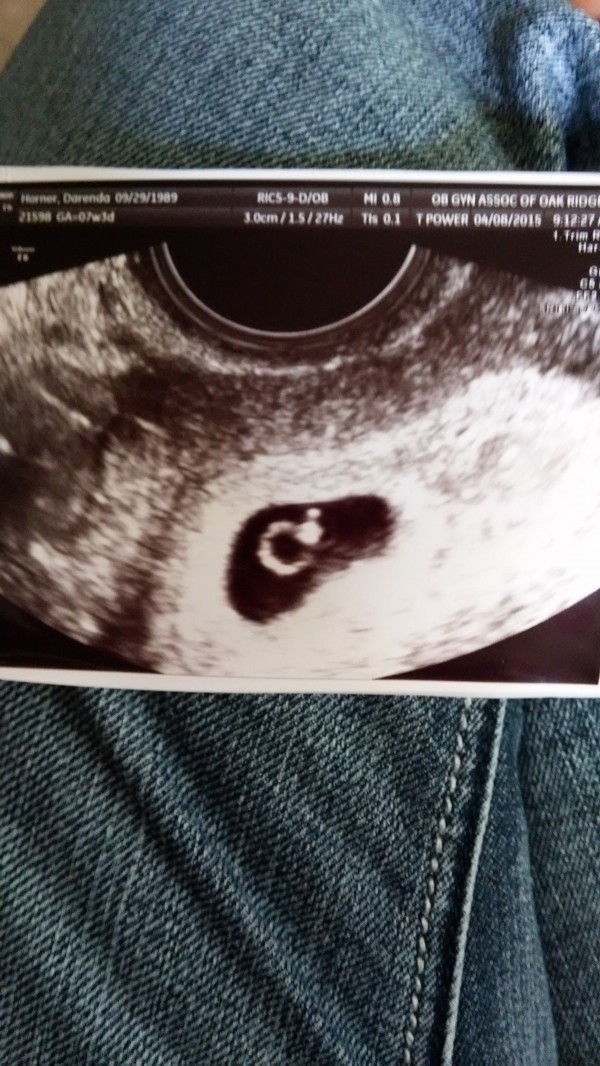

.x.Ultrasound

04/08/2015

TITLE HERE So, went for ultrasound. I'm 6 weeks today like I thought. The pic says 7 weeks 3 days but that's because they had it as my last period was February 15. Baby is right where it should be and heartbeat is 140. Due date is Dec. 3. I bought a girl onsite....but that's cause I know it's a girl. I'm going to feel real fucking stupid if it ain't lol.

April 8, 2015 - First ultrasound at OBGYN office to make sure baby is okay, and hopefully found out my due date. Baby is great, due Date is December 3, and the heartbeat was 140.